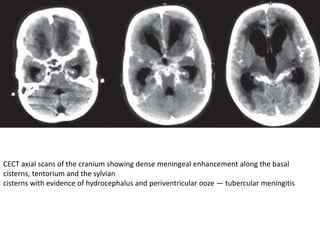

CECT axial scans of the cranium showing dense meningeal enhancement along the basal

cisterns, tentorium and the sylvian

cisterns with evidence of hydrocephalus and periventricular ooze — tubercular meningitis

CT

• Computed tomography shows obliteration by

isoattenuating or marginally hyperattenuating exudate

at the basal cisterns and plaque like dural thickening

• On intravenous contrast administration, there is dense

homogeneous enhancement of the basal cisterns

which may extend to the convexities, tentorium and

sylvian fissures

• ependymitis is seen as a linear enhancement along the

ventricular margins.

• The presence of hydrocephalus is thought to be related

to poor prognosis.